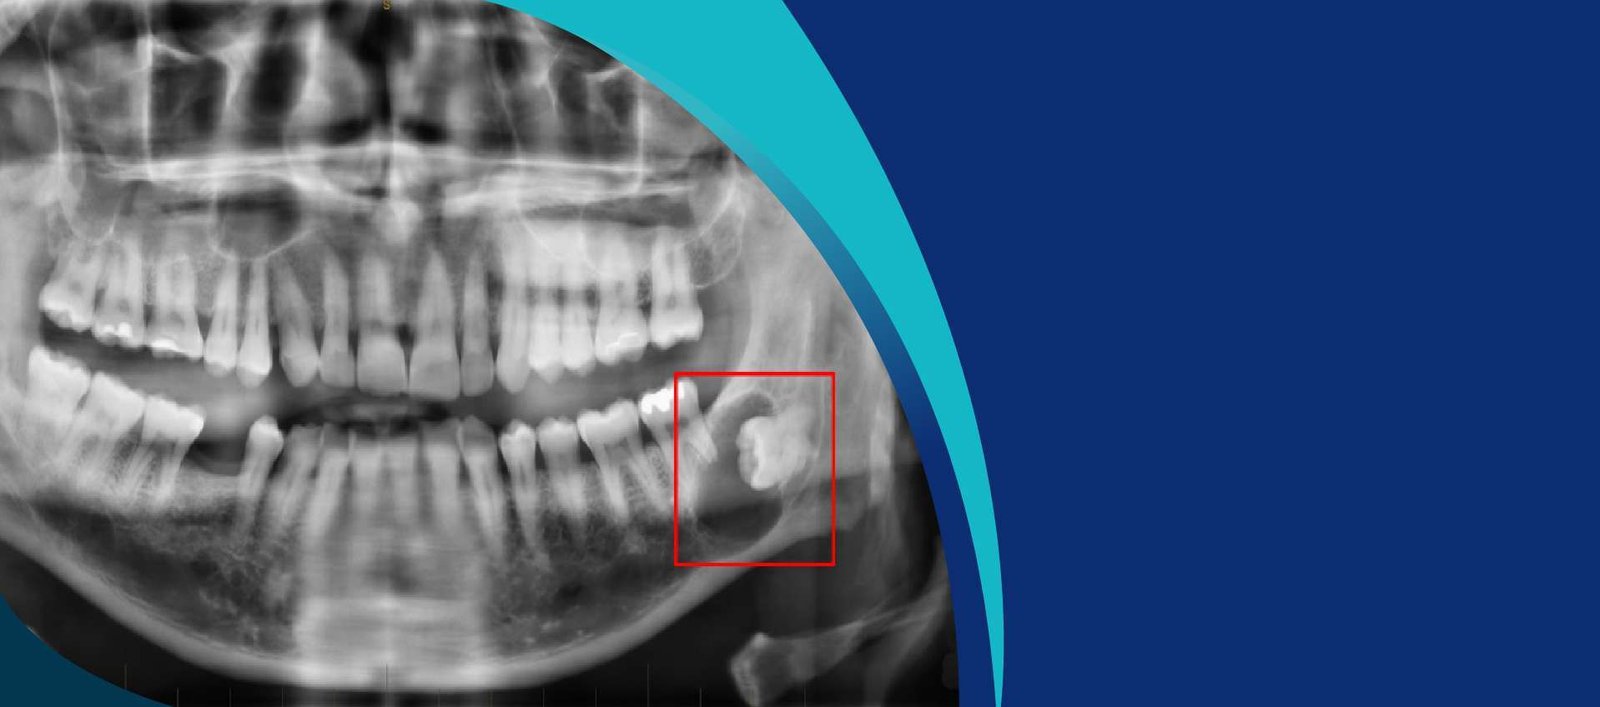

OPG, or Orthopantomogram, is a panoramic scanning dental X-ray of the upper and lower jaw. It provides a wide view of the jaw and teeth, capturing detailed images of the mouth, including the teeth, jawbones, and surrounding structures, in a single, comprehensive image. This technology is instrumental in diagnosing various dental conditions and planning treatments effectively.

• Comprehensive Diagnosis: OPG provides a complete view of your oral structures, enabling our dentists to detect issues such as impacted teeth, jaw fractures, and bone abnormalities.

• Early Detection: With detailed imagery, OPG allows for the early detection of dental problems, ensuring timely and effective interventions.